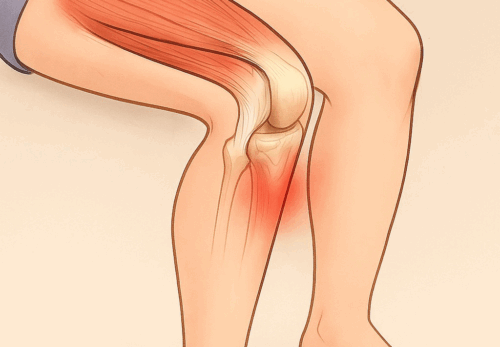

痛みが出やすい場所

アキレス腱の炎症は主に2つの部位に分けられます。

1.アキレス腱の中央部(腱の真ん中あたり)

・ふくらはぎと踵のちょうど間、腱の途中に炎症が起きるタイプ

・ランニングやジャンプの繰り返しで起こりやすい

・押すと硬くしこりのように感じることもある

2.アキレス腱付着部(かかとの骨に近い部分)

・踵の少し上、腱が骨にくっつく部分に炎症が出るタイプ

・シューズのかかとが当たって痛むことも多い

・骨の出っ張り(骨化や隆起)が伴う場合もある